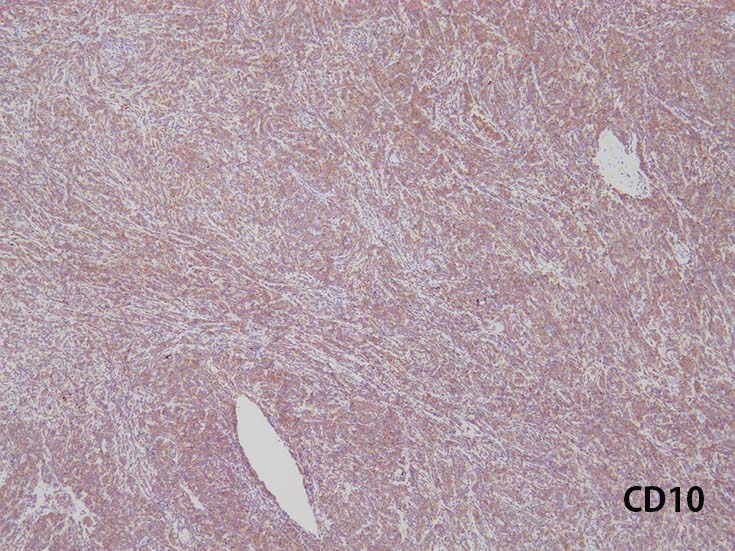

Immunophenotype of T-ALL/ LBL

- TdT, CD34に加えて, CD99と CD1a陽性はT-lymphoblastsの前駆細胞の性質を確認するのに役立つ.

- CD1a, CD2, surface CD3 (dim), CD4, CD5, CD8は種々の程度に発現する.

- T-ALL はしばしば, CD4とCD8の double positive となる. またCD10が陽性になる

- CD4,CD8 double positiveはT-prolymphocytic leukaemiaでも認められる. CD10もPTCL(第一にはAITL)に陽性となることに注意.